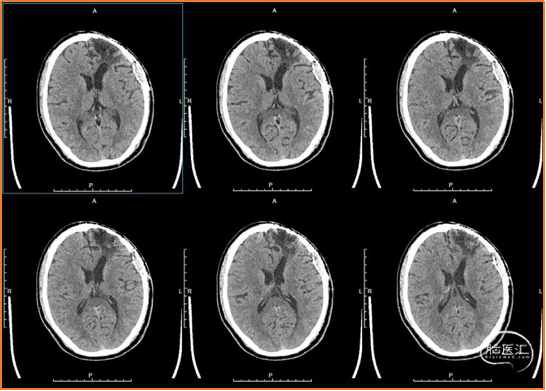

术前检查

术前诊断

1. 脑外伤后遗症,癫痫。

2. 颅骨修补材料凹陷。

诊疗方案

1. 去除钛网,重新行颅骨修补,修补材料为3D打印超高分子量聚乙烯(UHMWPE)网板。

2. 新修补材料植入颞肌下,嵌入骨窗内,恢复正常解剖层次,恢复容貌外观。

3. 显微手术切除额叶软化灶。